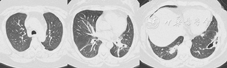

患者女,39岁,因右耳流脓2个月,发热、脓痰、皮下脓肿1个月于2013年5月入北京协和医院。2个月前右耳流脓、耳后胀痛、听力下降。1个月前发热,最高体温40 ℃,伴咳嗽,黄脓痰,偶痰中带血;出现皮下多发脓肿,累双侧乳房、右颌下、右腋下、右上臂、左腹壁等部位,破溃后流出红黄色脓液,恶臭。就诊于当地医院,检查示血常规:白细胞15.8×109/L,中性粒细胞80.9%,血红蛋白109 g/L,血小板537×109/L;红细胞沉降率(ESR) 75 mm/1 h;C反应蛋白(CRP)341 mg/L;胸部CT示双肺多发脓肿;头颅CT:双侧上颌窦、筛窦炎;结核抗体、脓液及痰培养阴性;右乳脓肿活检:乳腺脓肿伴肉芽肿形成;予哌拉西林/他唑巴坦等抗感染疗效不佳,为进一步诊治入北京协和医院。病来精神、饮食、睡眠差,体重下降10 kg。既往体健,曾饲养家禽。月经婚育、家族史无殊。体格检查:体温40 ℃,心率128次/min,血压130/80 mmHg(1 mmHg =0.133 kPa),血氧饱和度自然状态下92%,多发皮下脓肿破溃(图1),脓液流出,鼻梁背侧压痛明显,双肺呼吸音粗,心、腹部无特殊,双下肢无凹陷性水肿。实验室检查:血常规:白细胞11.73×109/L,血红蛋白96 g/L,血小板453×109/L;肝肾功:丙氨酸转氨酶462 U/L,白蛋白21 g/L,乳酸脱氢酶275 U/L;尿红细胞47.7/μl,尿红细胞畸形率90%,24 h尿蛋白1.0 g;降钙素元1.60 pg/L;G试验0.156 1 pg/L;皮损处脓液、鼻窦组织、痰、耳、鼻拭子培养,痰涂片及染色可见肺炎克雷伯杆菌、鲍曼不动杆菌、凝固酶阴性葡萄球菌、溶血孪生球菌及白念珠菌等多种细菌、真菌;结核抗体、血隐球菌抗原、GM试验、病毒血清学检查及血培养阴性。ESR 115 mm/1 h,超敏CRP 266.08 mg/L;抗中性粒细胞胞质抗体(ANCA):胞质型1∶20;蛋白酶3(PR3)-ANCA >0.2 RU/L;抗核抗体、抗可提取抗原抗体:阴性。胸部高分辨率CT(图2):右肺上叶结节、双肺多发团块软组织密度影,双肺门及纵隔多发淋巴结;鼻窦CT:鼻窦内广泛软组织影伴骨质破坏;颞骨薄层CT:双侧鼓室内弥漫密度增高影,右侧乳突骨质破坏,后颅窝面骨板不连续;内听道增强MRI:坏死性炎性病变可能。PET/CT:头面部多处代谢不均匀增高,双肺多发代谢异常增高的空洞及结节,皮下多发代谢增高灶,炎性病变可能性大,符合韦格纳肉芽肿。乳腺、皮肤及鼻中隔肿物活体组织检查均提示炎性肉芽肿,局部伴坏死脓肿形成及淋巴细胞浸润,可见局灶血管壁纤维增生。

诊断肉芽肿性多血管炎(GPA),继发皮肤感染。予甲泼尼龙48 mg/d口服及复方环磷酰胺(CTX) 100 mg/d口服,后改为CTX隔日0.2 g静脉滴注治疗原发病,予哌拉西林/他唑巴坦+复方甲氧苄啶抗感染,皮下脓肿破溃处定期以抗生素软膏、外用重组牛碱性成纤维细胞生长因子(融合蛋白)及红汞纱条换药。经上述治疗,仍有发热,将抗生素调整为万古霉素、头孢他啶、氟康唑、磺胺,加用人丙种球蛋白10 g/d静脉滴注,共5 d,体温仍无好转,最高体温39.4 ℃,头痛加重,出现右侧额纹消失,鼻唇沟变浅,口角左偏,伸舌左偏,悬雍垂左偏,头颅MRI提示双侧硬脑膜增厚并明显强化(图3),多发颅神经受累(Ⅶ、Ⅷ、Ⅸ、Ⅹ),行腰穿及脑脊液检查未见异常,诊断肉芽肿性多血管炎(GPA)、肥厚性硬脑膜炎(HCP)、颅神经受累,予甲泼尼龙1 g/d静脉滴注冲击治疗3 d,后序贯为40 mg/d静脉滴注;加强CTX使用,改为每周1 g,分3~4次静脉滴注,同时加用来氟米特20 mg/d口服;每周鞘内注射地塞米松10 mg,共3次,头痛明显缓解,体温降至正常。复查胸部高分辨CT见肺内空洞、占位较前缩小,停用抗生素。经治疗,体温正常,皮损大部分愈合,尿蛋白降至正常,肺部病变较前好转,ESR降至44 mm/1 h,超敏CRP降至9.59 mg/L,PR3-ANCA降至0.094 RU/L,静脉激素改为泼尼松50 mg/d口服,静脉CTX改为复方CTX 150 mg/d口服出院。出院后随诊至今,泼尼松逐渐减量,目前已减至泼尼松10 mg/d口服,半年后复查胸部CT(图4),多数结节、占位病变吸收或缩小,皮肤溃疡愈合(图5)。